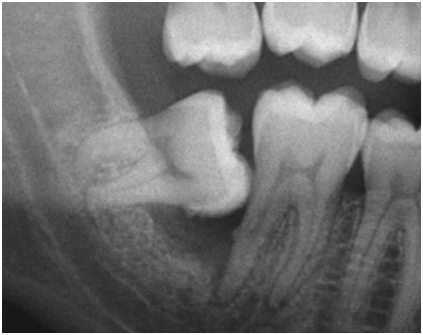

次の画像は、手前の歯の虫歯は確認されませんが、親知らずの頭の周辺が全体的に黒く抜けており、骨が溶けてしまっている状態です。これも親知らずが原因で、歯周病が進行した結果です。